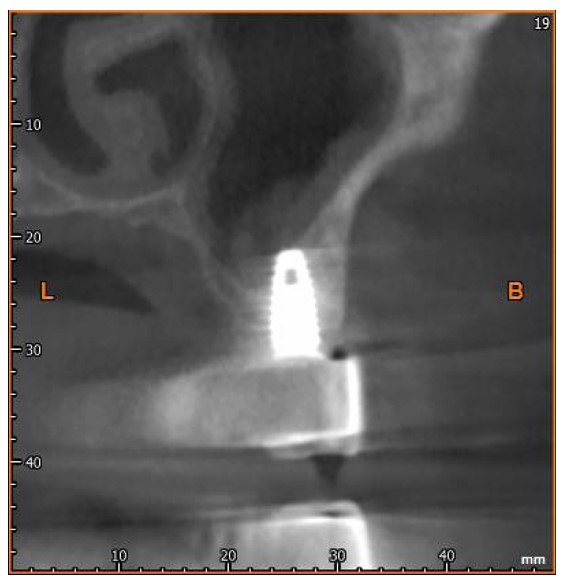

Histological examination revealed complete replacement of normal bone structure with a sclerotic osseous mass, including detectable Haversian systems. The diagnosis of idiopathic osteosclerosis was confirmed based on clinical, radiological, and histological findings (Fig. 2).

After six months, the implants were exposed, healing abutments were placed, and prosthetic procedures began (Figs. 3 and 4). The RFA of the implant within the lesion revealed a measurement of 83.

Histological examination of the radiopaque lesion confirming the diagnosis of osteosclerosis.

OPG 6 months after surgery showing the success of the dental implant placed within the osteosclerotic area.

CBCT scan 12 months after surgery.